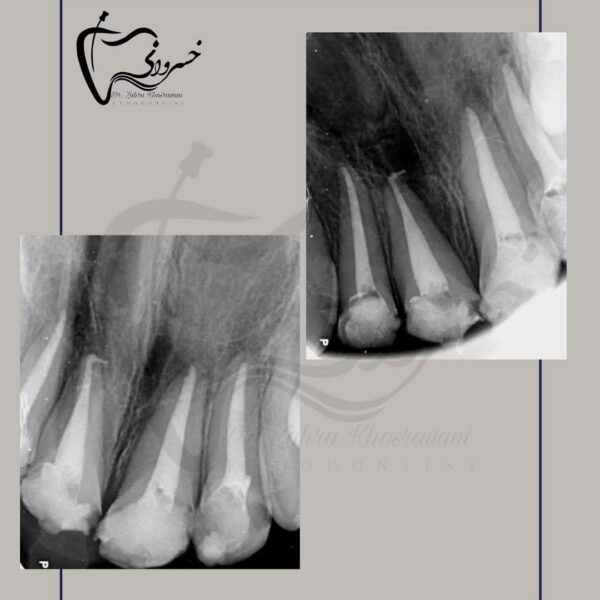

Cold ceramic plug